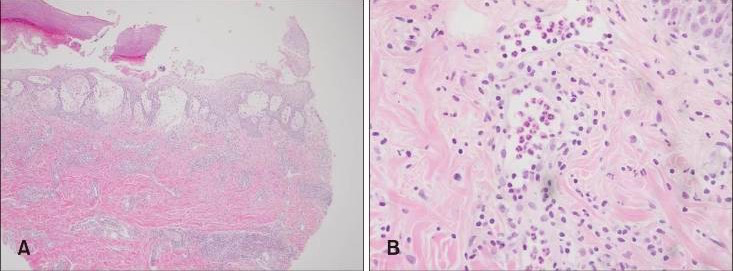

检查发现轻度乳头状真皮水肿,致密、弥漫性间质性皮炎,中性粒细胞占优势。革兰染色、高碘酸-希夫染色、淀粉酶、抗酸杆菌染色均没有发现微生物。皮肤活检标本与阴性组织培养的分析结果最符合急性中性粒细胞性皮肤病(Sweet 综合征)。

皮肤活检结果

图片来源:PubMed [3]